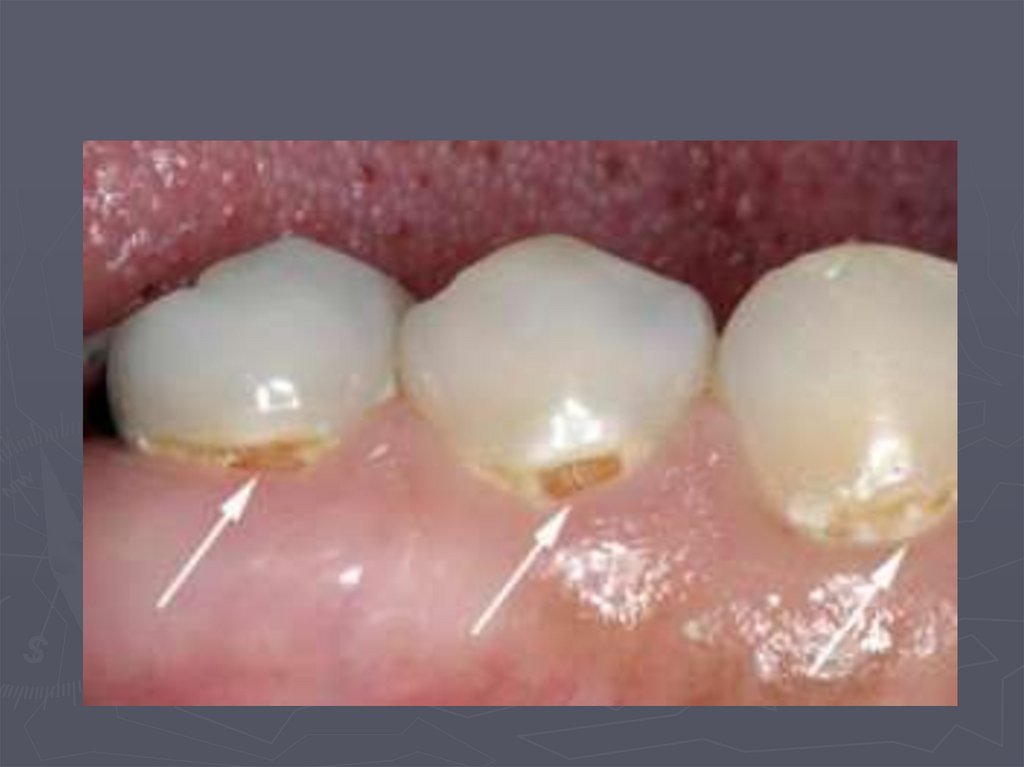

КЛИНИЧЕСКАЯ КАРТИНА ПОВЕРХНОСТНОГО КАРИЕСА

30. КЛИНИЧЕСКАЯ КАРТИНА ПОВЕРХНОСТНОГО КАРИЕСА

►отмечается быстропроходящая боль от

сладкого, соленого, иногда от

механических раздражителей;

►поверхность эмали зуба шероховатая;

►при зондировании определяется

неглубокий дефект;

►при зондировании может определяться

легкий дискомфорт.